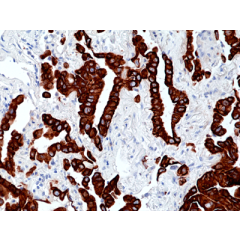

anti-Cytokeratin-8 (human), Rabbit Monoclonal (RM266)

anti-Cytokeratin-8 (human), Rabbit Monoclonal (RM266)

REV-31-1148-00 REV-31-1148-00-R100 100 µl CHF 468.00